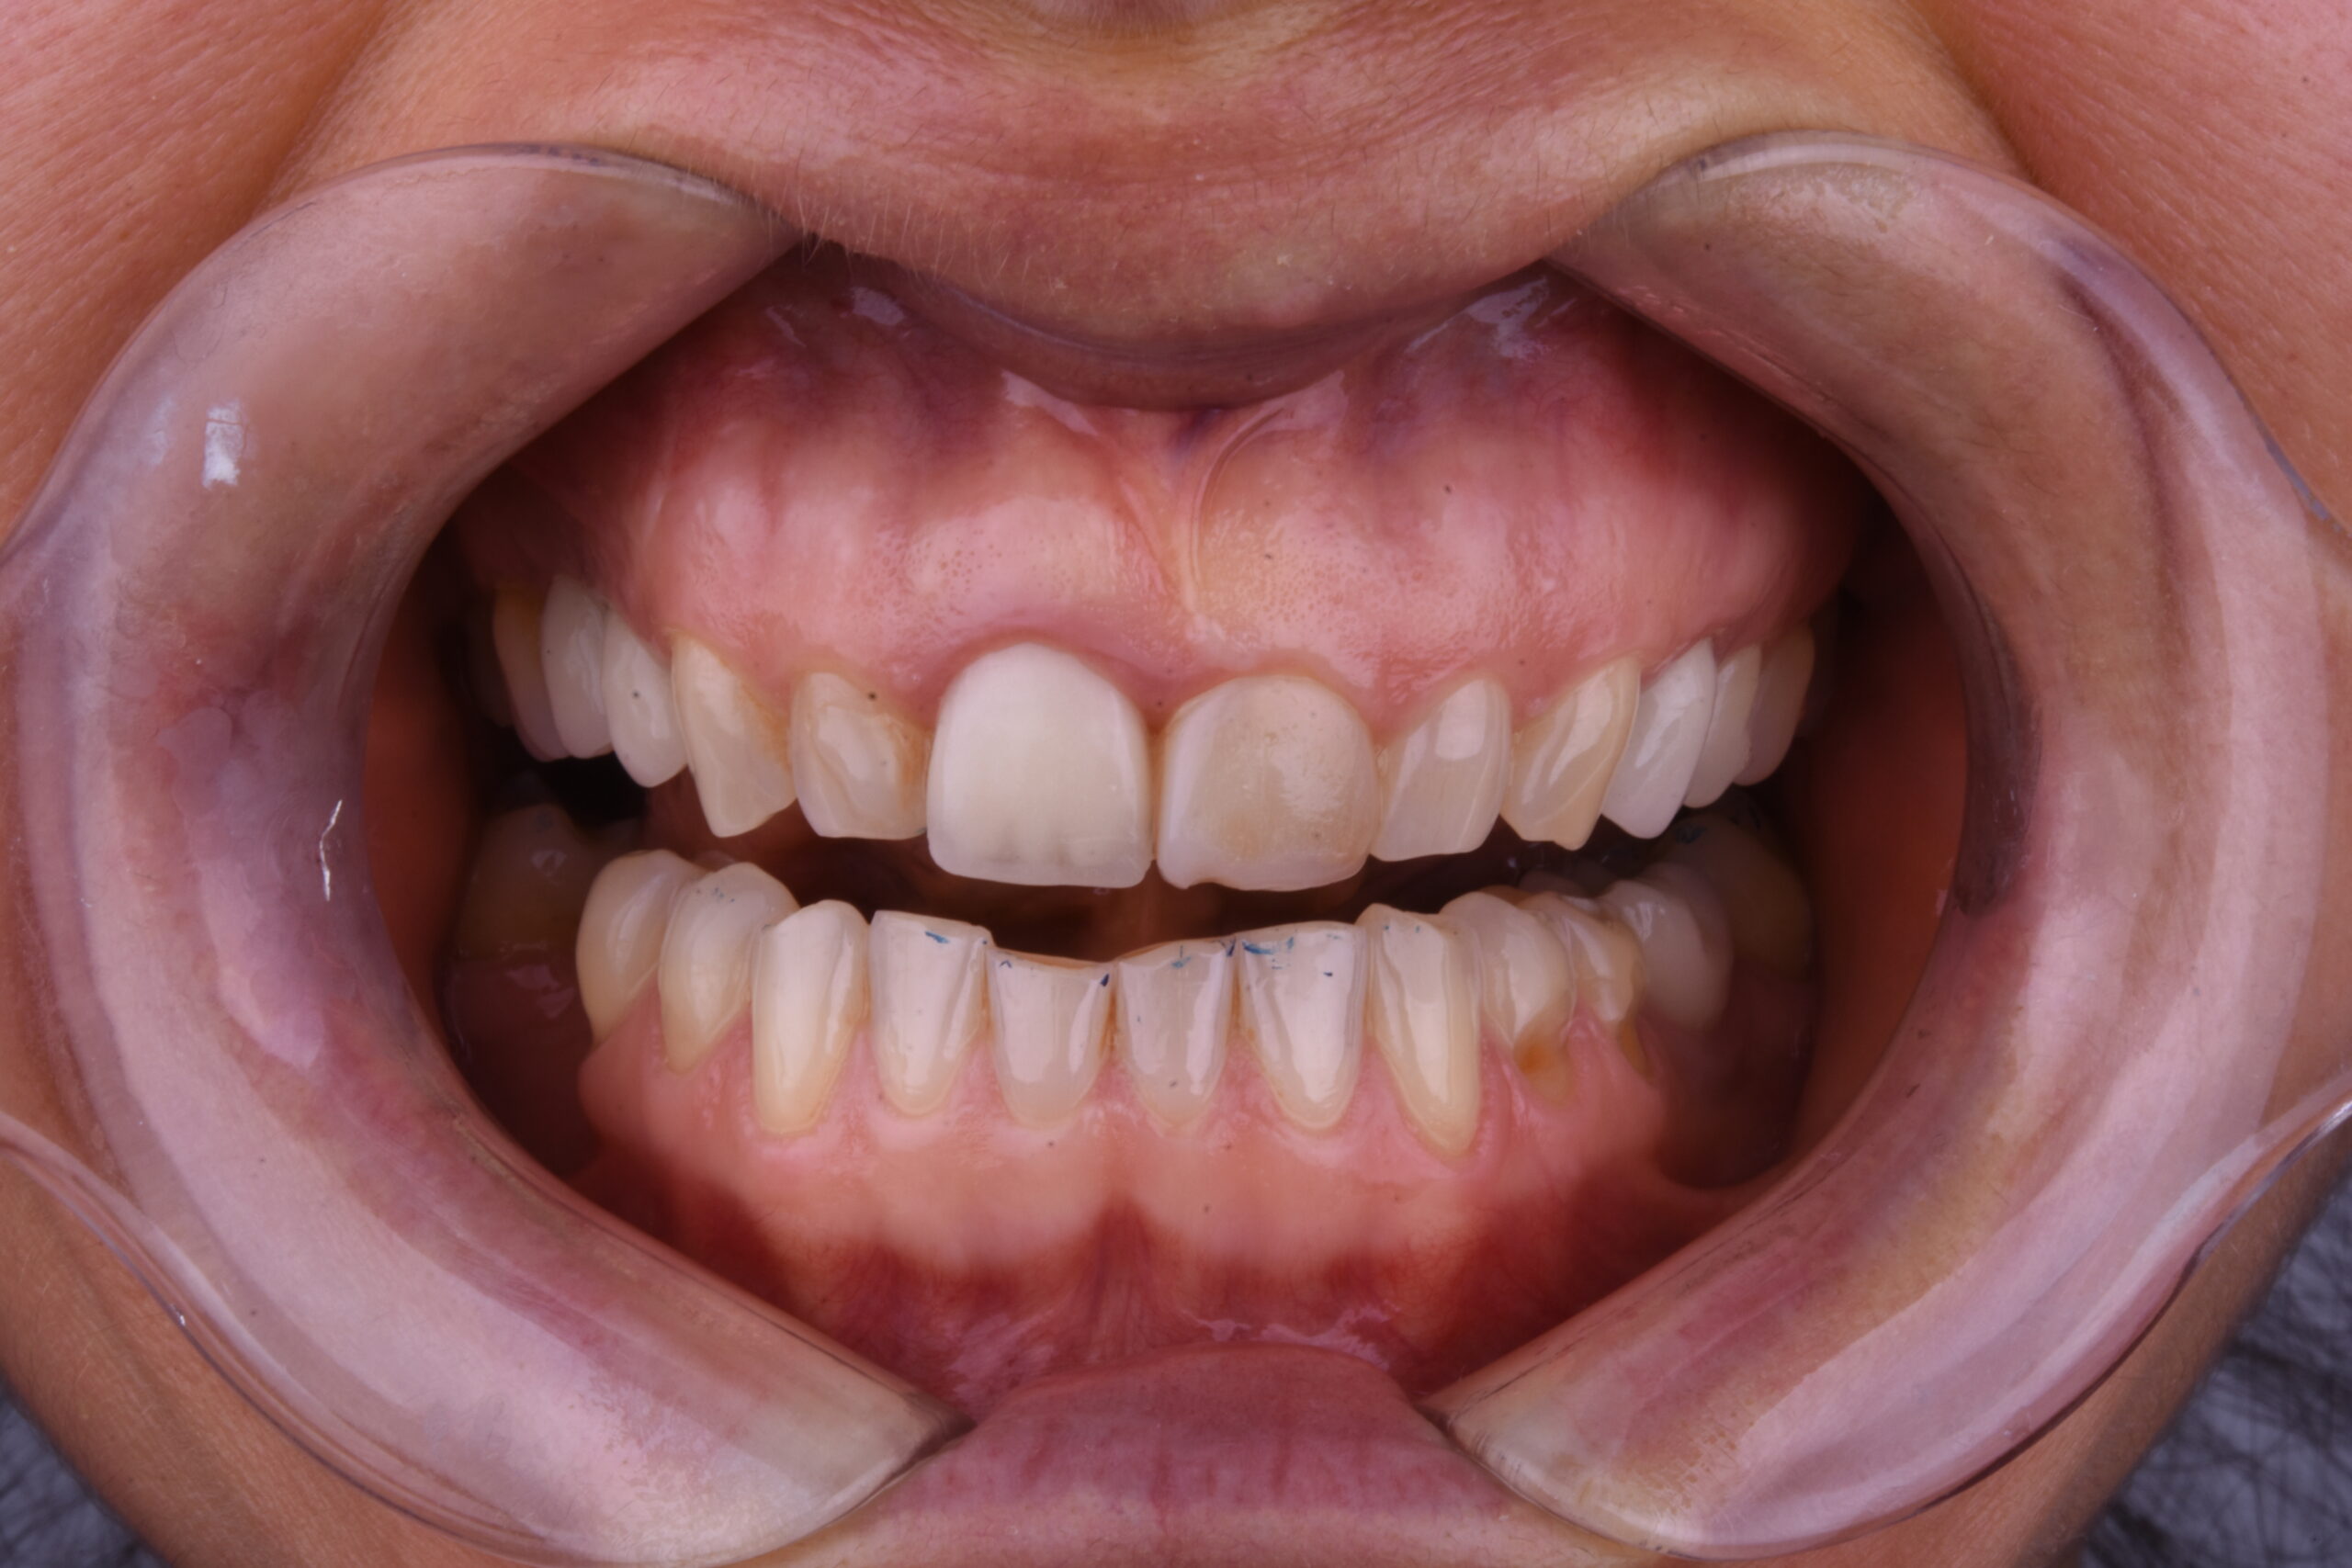

Resultados Resultados

Antes del tratamiento Sorriso depois do tratamento

Devolverle el alma y vestiral con una bella sonrisa como decia su madre consiguiendo esos dientes blanquitos que tanto deseaba, respetando una buena oclusion y dinamica mandibular